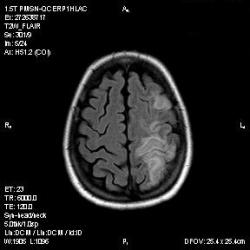

Из анамнеза - Женщина 45 лет. За год похудела на 15 кг (со слов матери), в последние месяцы случались эпизоды потери сознания. Онкозаболеваний и прочая в анамнезе нет. Сознание спутанное, из особенностей в анализах только подъем амилазы крови.

К сожалению, не владею методом КТ, но учитывая наличие неравномерного уплотнения в мозговых структурах с элементами очаговых "вкраплений", единственное, что приходит на ум - это рассеяный склероз. Хотелось бы уточнить, что беспокоило пациентку в течение последнего года кроме потери веса и эпизодов потери сознания? Была ли какая-либо очаговая неврологическая симптоматика? Отмечались ли какие-либо расстройства в двигательной или чувствительной сфере и т.д.? С уважением Helenmar.

И это точно не РС, т.к. характер очагов другой, ни один из них не копит контраст, нет субтенториальных очагов (извиняюсь, я этого в сообщении не указал), нет клиники.

"Раскрою" карты. Мы подумали о синдроме MELAS (mitochondrial encephalomyopathy, lactic acidosis and stroke) - дословно, митохондриальная энцефаломиелопатия, лактоацидоз и инсульт. В качестве дифференциальной диагностики можно было бы предположить вирусный энцефалит, но опять-таки, расположение очагов смущает - только с одной стороны и в абсолютно различных структурах.

В данном случае мы видим импульную последовательность FLAIR - режим с подавлением сигнала от воды, поэтому ликвор гипоинтенсивен, а также (вторая серия) - изображения, взвешенные по T1 после введения контрастного препарата. На T1 жидкость (ликвор) также представляется гипоинтенсивной. Зато на этих сериях гиперинтенсивны сосуды, т.к. контрастное вещество циркулирует в кровяном русле.

Изменения носят сосудистый характер. Процесс достаточно острый, имеется объемное воздействие, борозды левой гемисферы компремированы. По поводу MELAS синдрома очень сомневаюсь, почему поражена только левая гемисфера? Надо делать МР-ангиографию, смотреть нет ли стеноза

MELAS синдром - дебютирует с детских лет, характерен целый комплекс неврологических проявлений, заболевание генетическое, поражение системное, хотя есть множество вариантов митохондриального поражения, все же сомнительно. Хотелось бы акцентировать внимание, что гиперинтенсивные очаги есть в мозолистом теле, поражены выражено перивентрикулярные отделы, U -пути, белое вещество, поэтому так категорично демиелинизацию не вычеркивала бы из дифряда ( хотя тоже нетипично односторонее поражение). Думаю, для объективных выводов все же мало общей информации о пациентке, были ли клинические эпизоды раньше, чем объяснить такую потерю веса (возможно есть проявление паранеопластического синдрома?). Ну и МРТ-контроль в динамике, ангиография.

Да, неоднозначный случай. Точно не РС и не ОНМК. Я бы написала асимметричную лейкоэнцефалопатию неясного генеза. Можно было бы думать о лимфоме (полифокальное поражение, да еще мозолистое тело вроде бы задействовано (эх, сагиттальчики бы)). Но! Учитывая отсутствие накопления КВ.... Ну и надо исключать интоксикацию, всяческие аутоиммунные процессы (в т.ч. и васкулиты), сахарный диабет, ну и естественно наследственную патологию обменных процессов. УУУх! Вот.......

Имхо ишемический онмк в бассейне сма. Особенно показательны 5-й и 6-й файлы, отграничение как раз на границе бассейнов средней и перикаллёзной. Плюс одностороннее поражение.